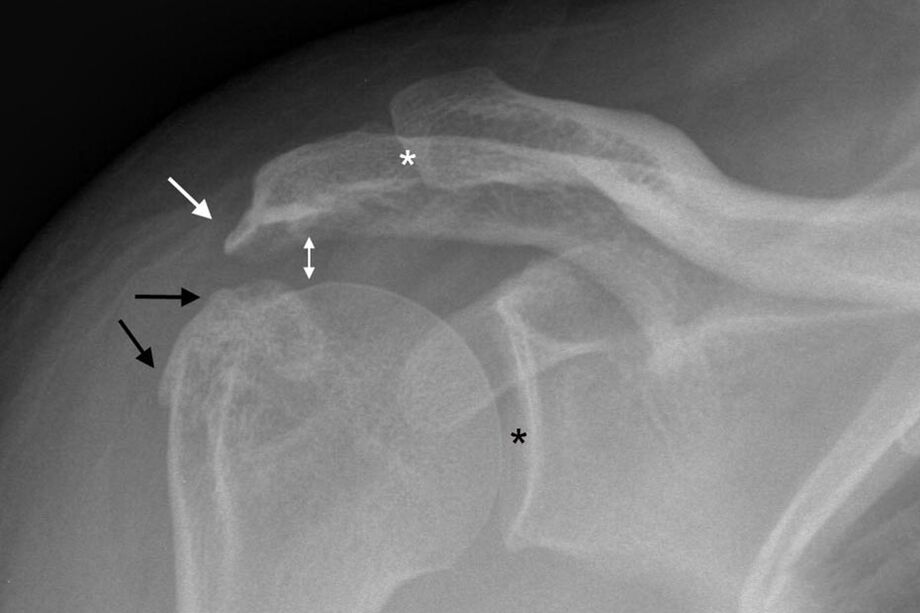

Osteoartrózu ramenního kloubu lze diagnostikovat pomocí standardního rentgenového snímku ramene. Snímek je pořízen ve dvou projekcích. Lékař diagnostikuje onemocnění za přítomnosti takových faktorů, jako jsou:

- Zúžení kloubní štěrbiny;

- Tvorba osteofytů;

- Skleróza kostní tkáně.